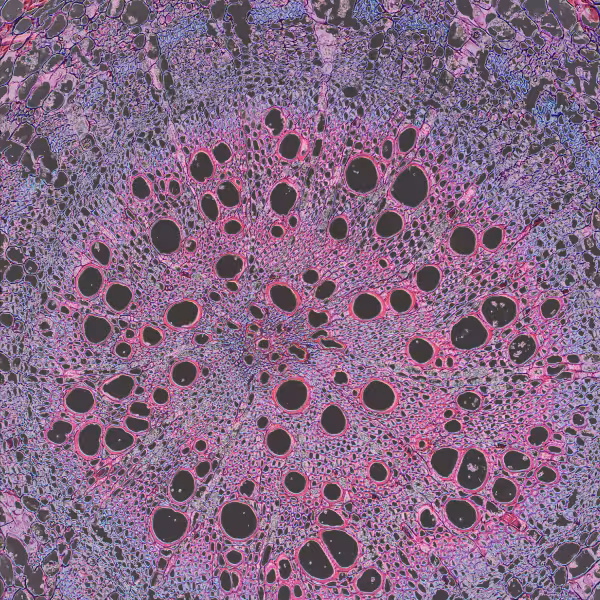

Blood diseases we test

Autoimmune and Inflammatory Diseases

Blood testing for Cancer-Associated Inflammation tracks immune–inflammatory balance that influences tumor behavior and prognosis (neutrophil–lymphocyte ratio, platelet–lymphocyte ratio, systemic immune-inflammation index, systemic inflammation response index: NLR, PLR, SII, SIRI). Superpower offers in-clinic and at-home testing; home collection is currently available in selected states. (See FAQs below for more info).

Blood tests help confirm Kawasaki Disease’s systemic inflammation and vascular involvement. CRP and ESR track acute inflammation, WBC signals immune activation, and platelets reflect later-phase thrombocytosis. At Superpower, we provide CRP, ESR, WBC, and Platelet testing in-clinic and at home. Home testing available in selected states. (See FAQs below for more info).

Blood testing clarifies inflammatory activity in rheumatoid arthritis, guiding diagnosis and monitoring disease burden. At Superpower, we measure ESR, CRP, Albumin, and derived ratios FAR and CAR to quantify systemic inflammation. We offer in-clinic and at-home testing; home collection is currently available in selected states. (See FAQs below for more info).